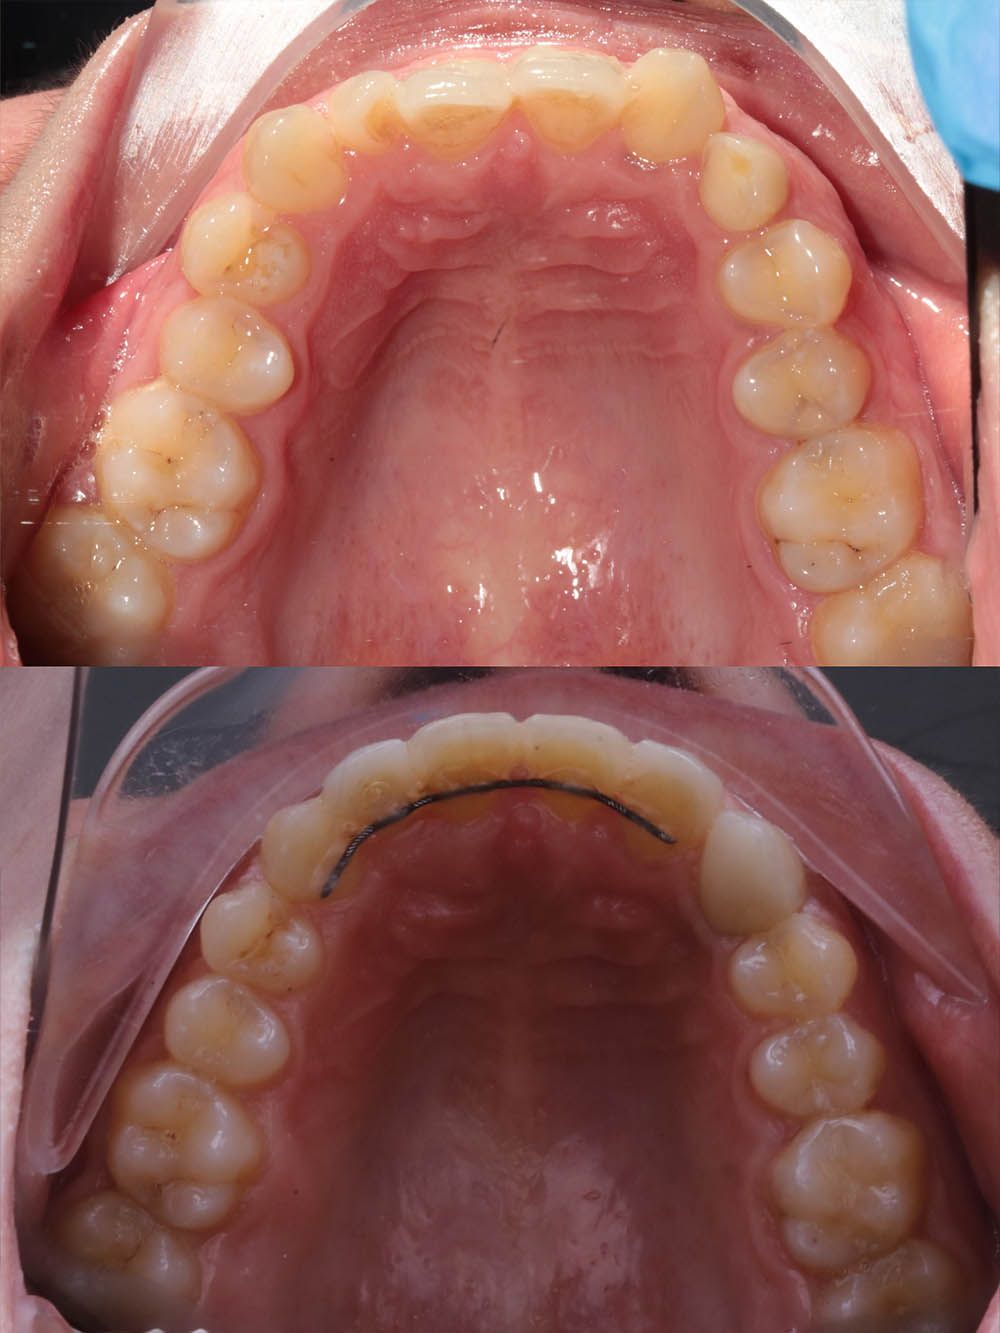

9 месяцев лечения на элайнерах

9 месяцев лечения на элайнерах

9 месяцев лечения на элайнерах